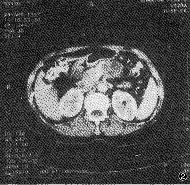

2.1.1 胰腺内异常CT表现:见表1。①病变区胰腺肿大,形成肿块(图1),表现为病变区前后径增大与局限性超出邻近正常胰腺3mm以上的隆起,癌组具有此类表现者49例,癌肿多发生于胰头区(39/49,69.39%)。②病变区密度异常:平扫病变区表现等密度、低密度、低与等混杂密度和更低密度的液化坏死灶。增强扫描绝大多数病灶(49/50,98%)显示为不均匀强化,呈低、等与等混杂和液化坏死的低密度灶(图2)。③胰管扩张:本癌组中胰管扩张率为80%,扩张的胰管均位于肿块的胰尾侧。

图2 胰腺囊腺癌,增强CT示胰体局限性增大,呈低、等混杂密度,中间 有多个液化坏死灶